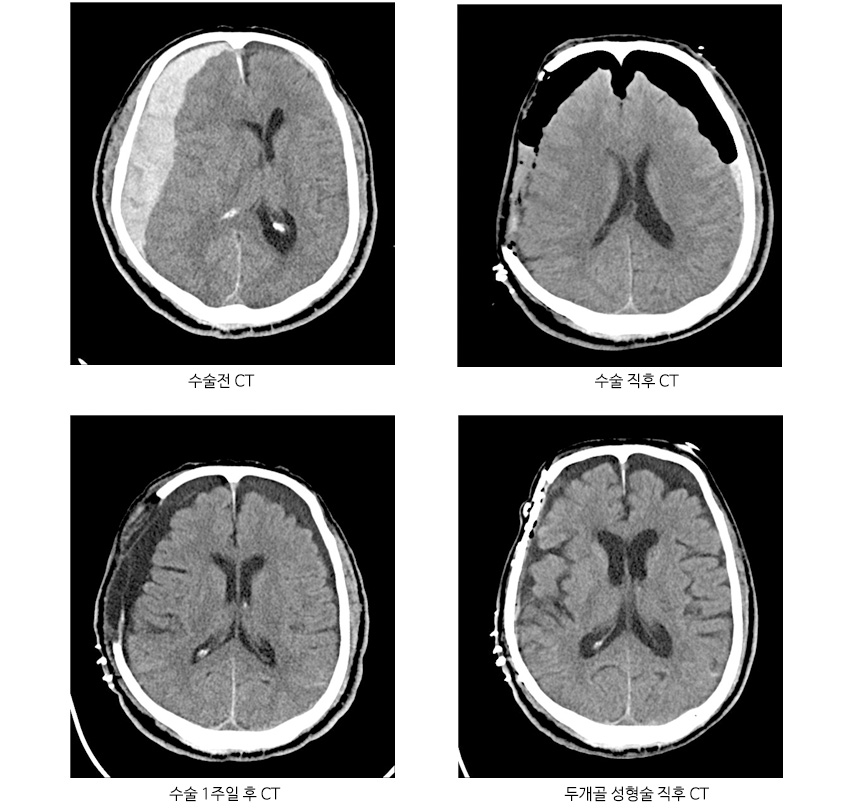

두개골성형술을 시행한 급성 경막하출혈 CT

치료는 환자의 상태에 따라 치료법이 달라지며 출혈량이 적고 환자의 의삭상태가 양호한 경우 뇌CT를 촬영하여 지속적으로 관찰할 수 있으며, 출혈량이 많고 뇌부종이 심하여 조절이 안되는 경우 천두술, 개두술을 이용하여 경막을 열어 응고 출혈을 제거하고 제거하더라도 뇌부종이 올라가는 경우 감압술을 시행합니다.

뇌출혈을 진단하기 위해서는 CT 및 MRI 등으로 두개강내의 출혈 여부를 확인할 수 있으며, 뇌지주막하 출혈이 생긴 경우 뇌혈관조영검사를 통하여 진단합니다.